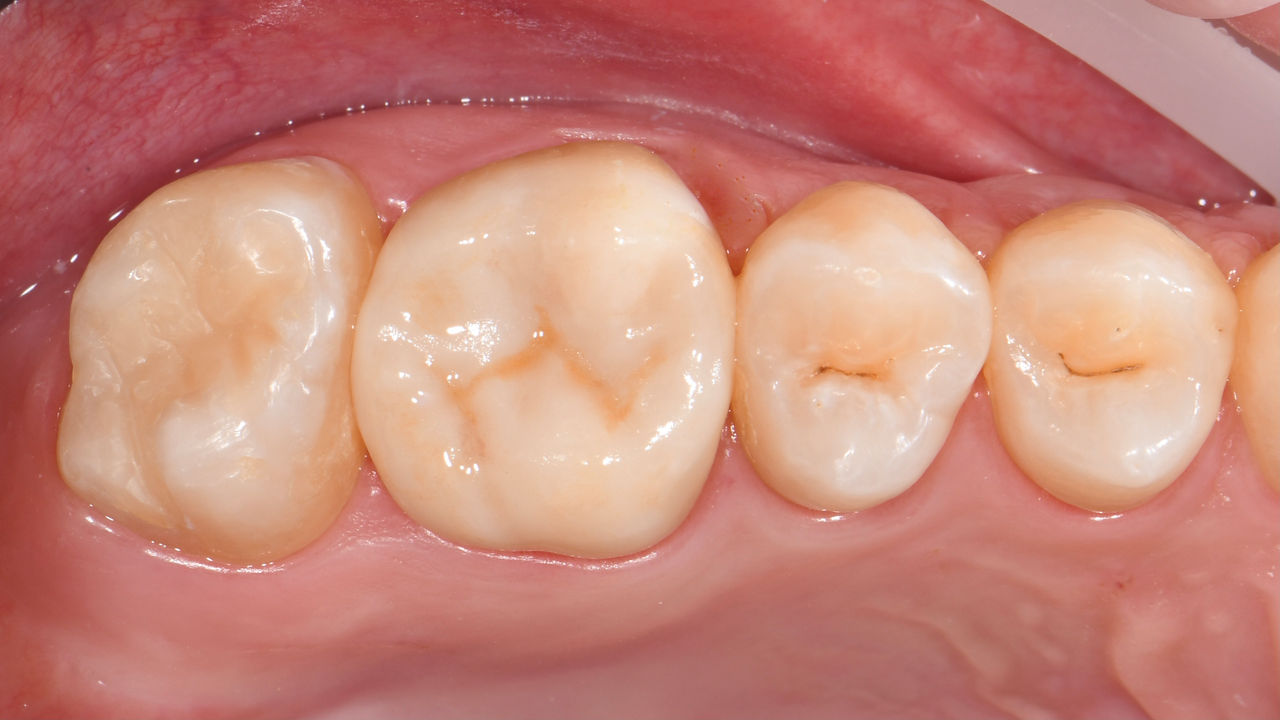

Second lower right molar in 90 minutes

A CEREC Tessera onlay

A 20-year-old female patient had endodontic treatment of her lower right 2nd molar. A chairside onlay was fabricated from the new high-strength ceramic CEREC Tessera ALD.

Before: Pre-operative clinical scenario after endodontic therapy.

After: 1 month after the CEREC Tessera onlay was bonded.

Dr. Aniruddha Nene

Pune, India